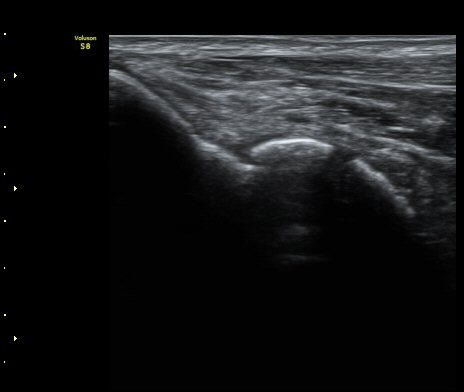

ÃÊÀ½ÆÄ °Ë»ç